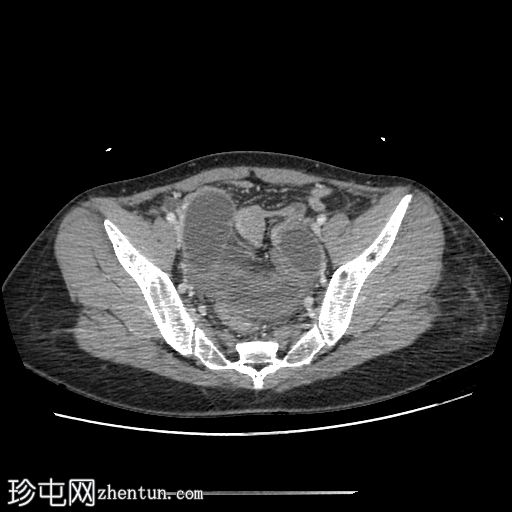

轴位增强扫描(门静脉期)

小肠袢明显扩张,左侧附件区可见双移行点,远端回肠短段闭袢梗阻,肠颈位于左侧输卵管/左侧子宫血管附近。

肠系膜血管充血,腹盆腔可见游离液体,提示肠系膜充血。

远端回肠袢和结肠已减压。

无肠缺血或穿孔的影像学证据。